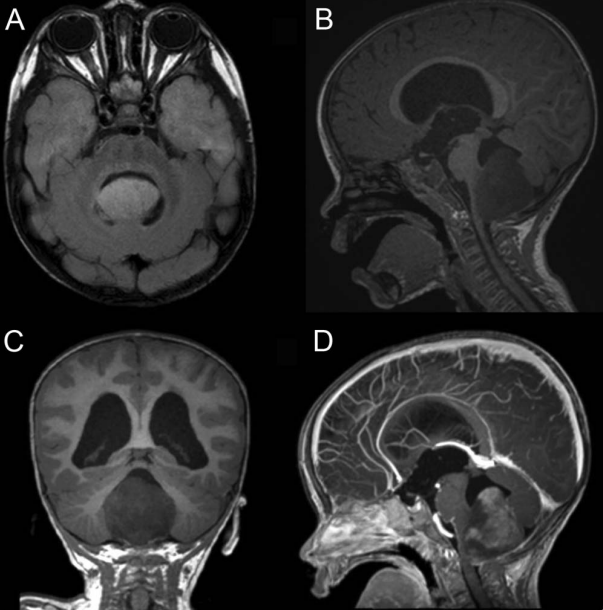

间脑综合征是一种少见的临床表现,传统上包括严重的发育障碍、眼球震颤和运动过度,继发于典型的位于下丘脑及其附近的颅内肿瘤。然而,其临床表现是多种多样的,往往导致诊断...